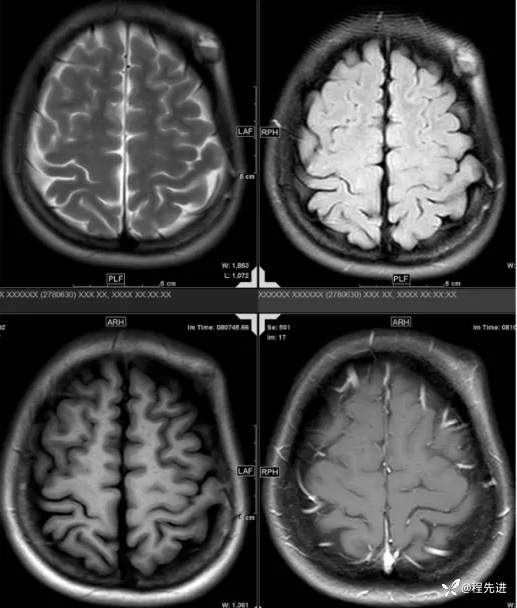

【患者信息】:女,31岁

【主诉】:发现头部肿物1月余

【现病史及既往史】:患者自诉于1月前无明显诱因出现左额颞部肿块,大小约3*3cm,伴疼痛红肿发热,遂至我院外科门诊就诊考虑“局部感染”,予以对症治疗后,肿块疼痛红肿好转,但肿块无明显缩小。

【检查】:常规检验项目均(-)